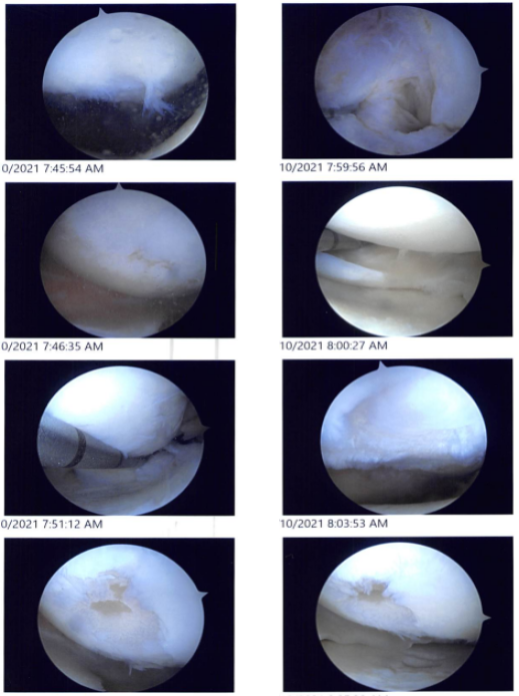

Case Study: Knee Arthroscopy: Medial Meniscal Repair in a 54 year-old female

Examination of the patellofemoral joint showed a grade I to grade II patellofemoral arthritis. Examination of the medial compartment showed a medial meniscus tear near the root. A medical entry portal was made with the use of a spinal needle. The probe was inserted to further examine.

The medial meniscus root was found to be intact. The shaver was used to shave the root with the use of a straight biter and bitters to do a meniscectomy of the medial meniscus.

The osteochondral lesion of the medial femoral condyle was debrided with the use of a shaver. The abrasion chondroplasty was performed over the medial femoral condyle.

Examination of the intercondylar notch showed a degenerative ACL, but the ACL was intact. Examination of the lateral femoral condyle showed a radial margin degenerative tear of the lateral meniscus, which was removed with the use of a shaver.

Examination of the patellofemoral compartment showed an osteochondral lesion, which was debrided with the use of a shaver. Final pictures were taken and saved. The knee was thoroughly irrigated and drained.

Intraoperative images